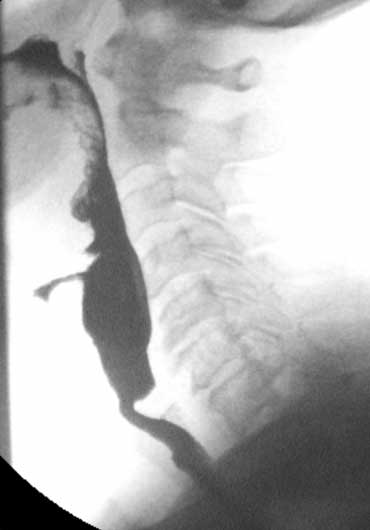

Ứ đọng (2)

Đây là bộ hình ảnh minh họa một bệnh nhân bị liệt các cơ khít hầu.

Tình trạng này thường đi kèm với giãn không đủ của cơ nhẫn hầu.

Trong ví dụ này, chúng ta có thể thấy bệnh nhân cố gắng bù đắp cho sự mất chức năng co bóp hầu bằng cách cử động quá mức của lưỡi và đầu.

Bệnh nhân này đang trong tình trạng căng thẳng cực độ, vì biết rằng khi bắt đầu thở mà cổ họng chưa trống, sẽ bị hít sặc.

- 1-3. Không thấy co bóp của thành sau hầu họng. Cơ nhẫn hầu không mở đúng cách.

- 4-7. Thuốc cản quang vào thanh quản nhưng không vào khí quản.

- 8-10. Cử động đầu quá mức nhằm đẩy bolus vào thực quản.

Trong một số trường hợp này, phẫu thuật cắt cơ nhẫn hầu là giải pháp duy nhất để tạo điều kiện cho thức ăn đi vào thực quản.